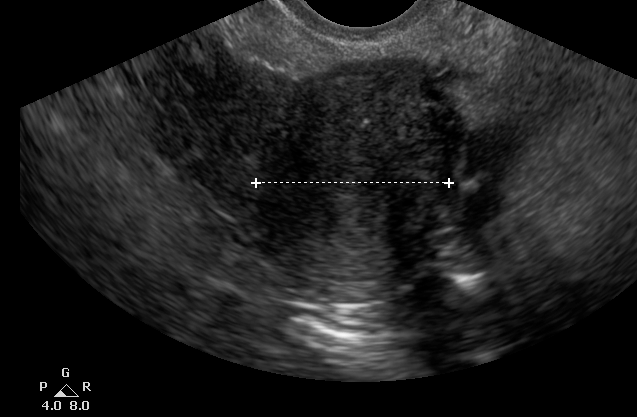

Lina в Зачатие 7 лет Это что? Желтое тело? Ваше мнение, что это? 3×2×2 Посмотрите еще 20 записей на эту тему Отменить Ответить Счастье Киста жёлтого тела, судя по размеру. 13.09.2018 Ответить Lina Спасибо 13.09.2018 Ответить Barbara А вам что ничего не сказали? Может киста ? 🤷🏼♀️ 13.09.2018 Ответить Lina В заключении просто написано в яичнике образование непонятного поисхождения. И размеры. 13.09.2018 Ответить Кристина. А не много ли это для жт? 3*2*2? 12.09.2018 Ответить Lina Не знаю. :( в яичнике нашли 12.09.2018 Ответить Чуда не случилось Какой день считать началом цикла? Чаты Беременных Выберите чат: Январята-2026 Февралята-2026 Мартята-2026 Апрелята-2026 Майчата-2026 Июнята-2026 Июлята-2026 Августята-2026